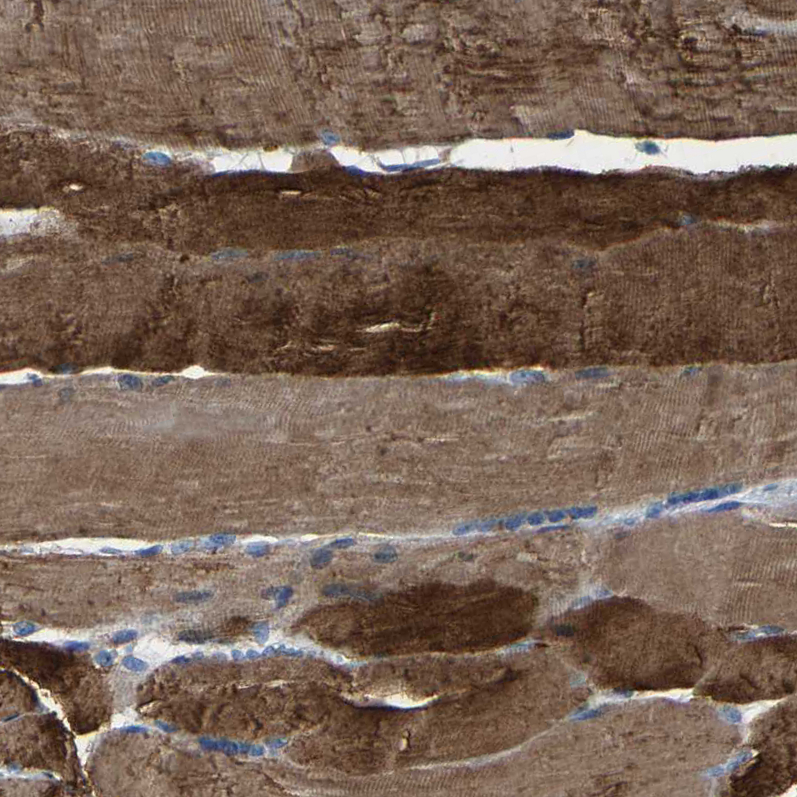

Immunohistochemical staining of human skeletal muscle shows strong cytoplasmic positivity in myocytes.